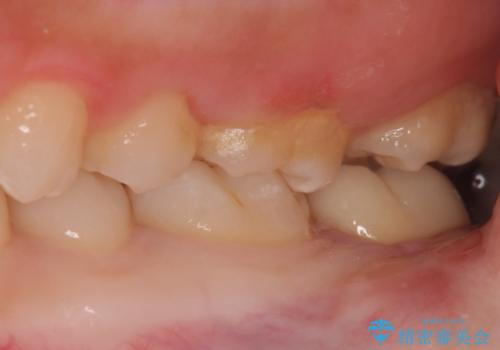

- 左下奥歯が痛いとの事で来院。

親知らずが炎症を起こしていたので抜歯をし、手前の歯は拡大鏡下で虫歯を取り除き、ジルコニアクラウンで治療をしました。

親知らずは歯ブラシがしにくく、虫歯のリスクが高いです。

手前の歯が虫歯になる前に抜歯をする事をお勧めします。